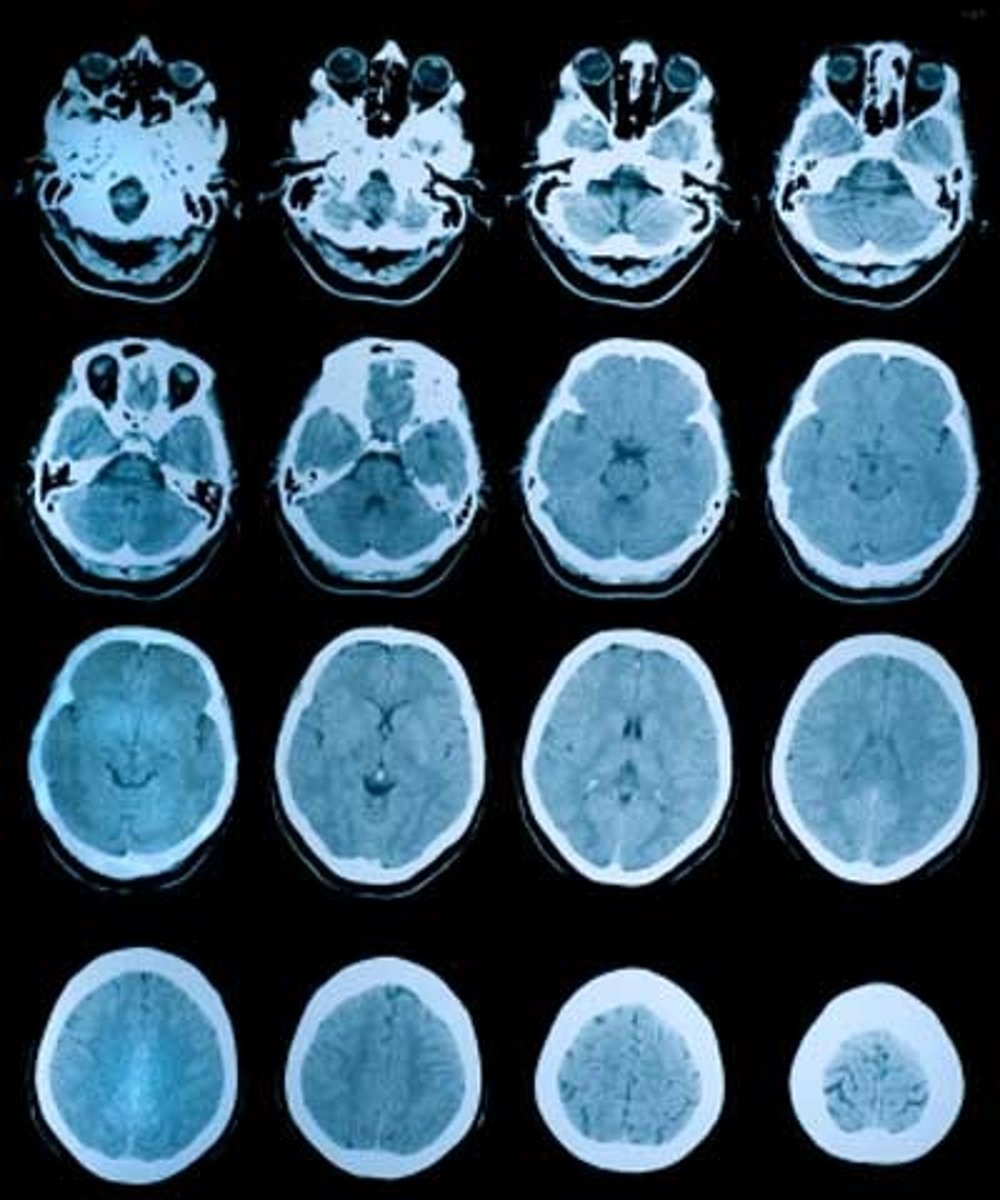

tomography

process of recording slices (anatomical cross section)